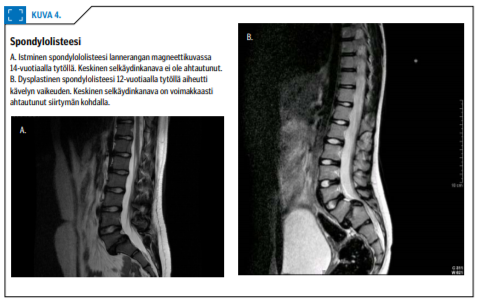

Pienelle osalle potilaista kehittyy nikaman siirtymä eli istminen spondylolisteesi (kuva 4A «»6) (8,9). Kasvu vaikuttaa siirtymän lisääntymisen riskiin (8). Lapsuusiässä leikkaushoitoa tarvitaan, kun siirtymä kehittyy suuriasteiseksi (yli 50 % nikaman pituudesta) tai potilaalla on hankala alaraajoihin säteilevä selkäkipuoireisto.

Spondylolisteesin taustalla voi myös olla synnynnäinen fasettinivelten vajaakehitys, jolloin nikaman siirtyessä myös keskinen selkäydinkanava ahtautuu (kuva 4B «»6). Useimmille potilaille kehittyy tällöin kipuskolioosi tai kävelyn vaikeus. Hoitamaton suuriasteinen spondylolisteesi voi edetä kasvuikäisellä spondyloptoosiin.